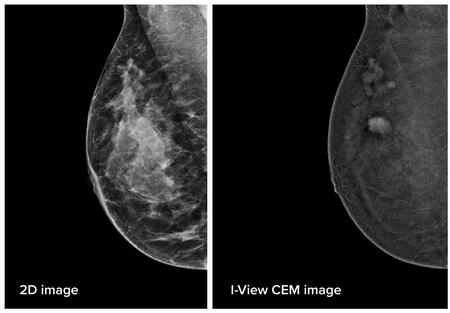

Randallstown, MD - Northwest Hospital is now offering Contrast Enhanced Mammography (CEM), a technology designed to detect cancers that may not be visible on a traditional mammogram. CEM exams are typically performed following an initial mammogram or ultrasound to gather more information about an area that appears abnormal, especially for patients that cannot have breast MRI.

CEM differs from a traditional mammogram in that patients receive an IV injection of an iodinated dye, the same as CAT scan, called a contrast agent. The dye flows into the breast tissue and draws attention to areas of interest, much like a highlighter marker emphasizes a specific word or sentence on a page.

“CEM allows a physician to get a different and enhanced view of an area of interest in the breast. The use of the contrast agent highlights where cancers may be forming, including new blood vessels that form when cancer is growing. CEM provides additional information beyond a traditional mammogram, which can lead to earlier detection of some cancers,” explains Niloofar Hakakian M.D., radiologist and medical director of Breast Imaging at LifeBridge Health.

She adds, “The sensitivity of traditional mammogram can drop to 50% for evaluation of the denser breast tissue, which means the early cancer may not be visible as it can hide behind the white dense tissue. CEM can be added to annual mammogram in women with dense breast tissue and high-risk population to help detecting cancer early. The contrast in CEM makes a better distinction between dense breast tissue and abnormalities, leading to the possible earlier detection of some cancers for women with this type of dense tissue.”